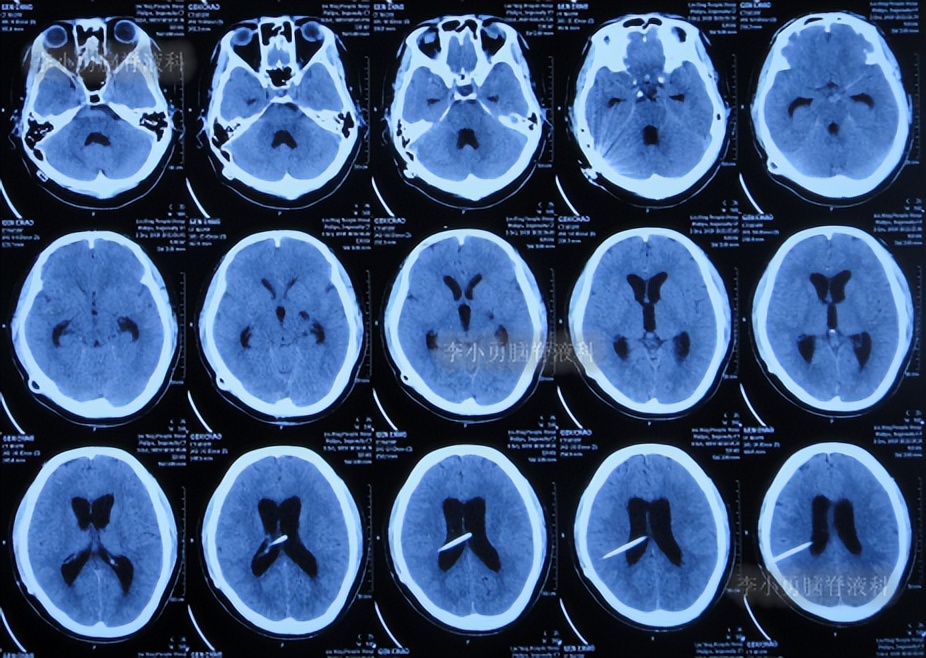

出院后1年半期间,仍时有视物重影的症状,并未给予处理,但到2019年9月27日(脑室腹腔分流术后1年零6个半月),出现头晕,恶心呕吐,视物重影加重,5天后因症状无缓解,就诊于当地的河南省临颍县某医院,查脑CT示脑积水(图-1);给予腰穿检查示颅内压力高220mmH2O。

图-1:2019年10月3日头颅CT